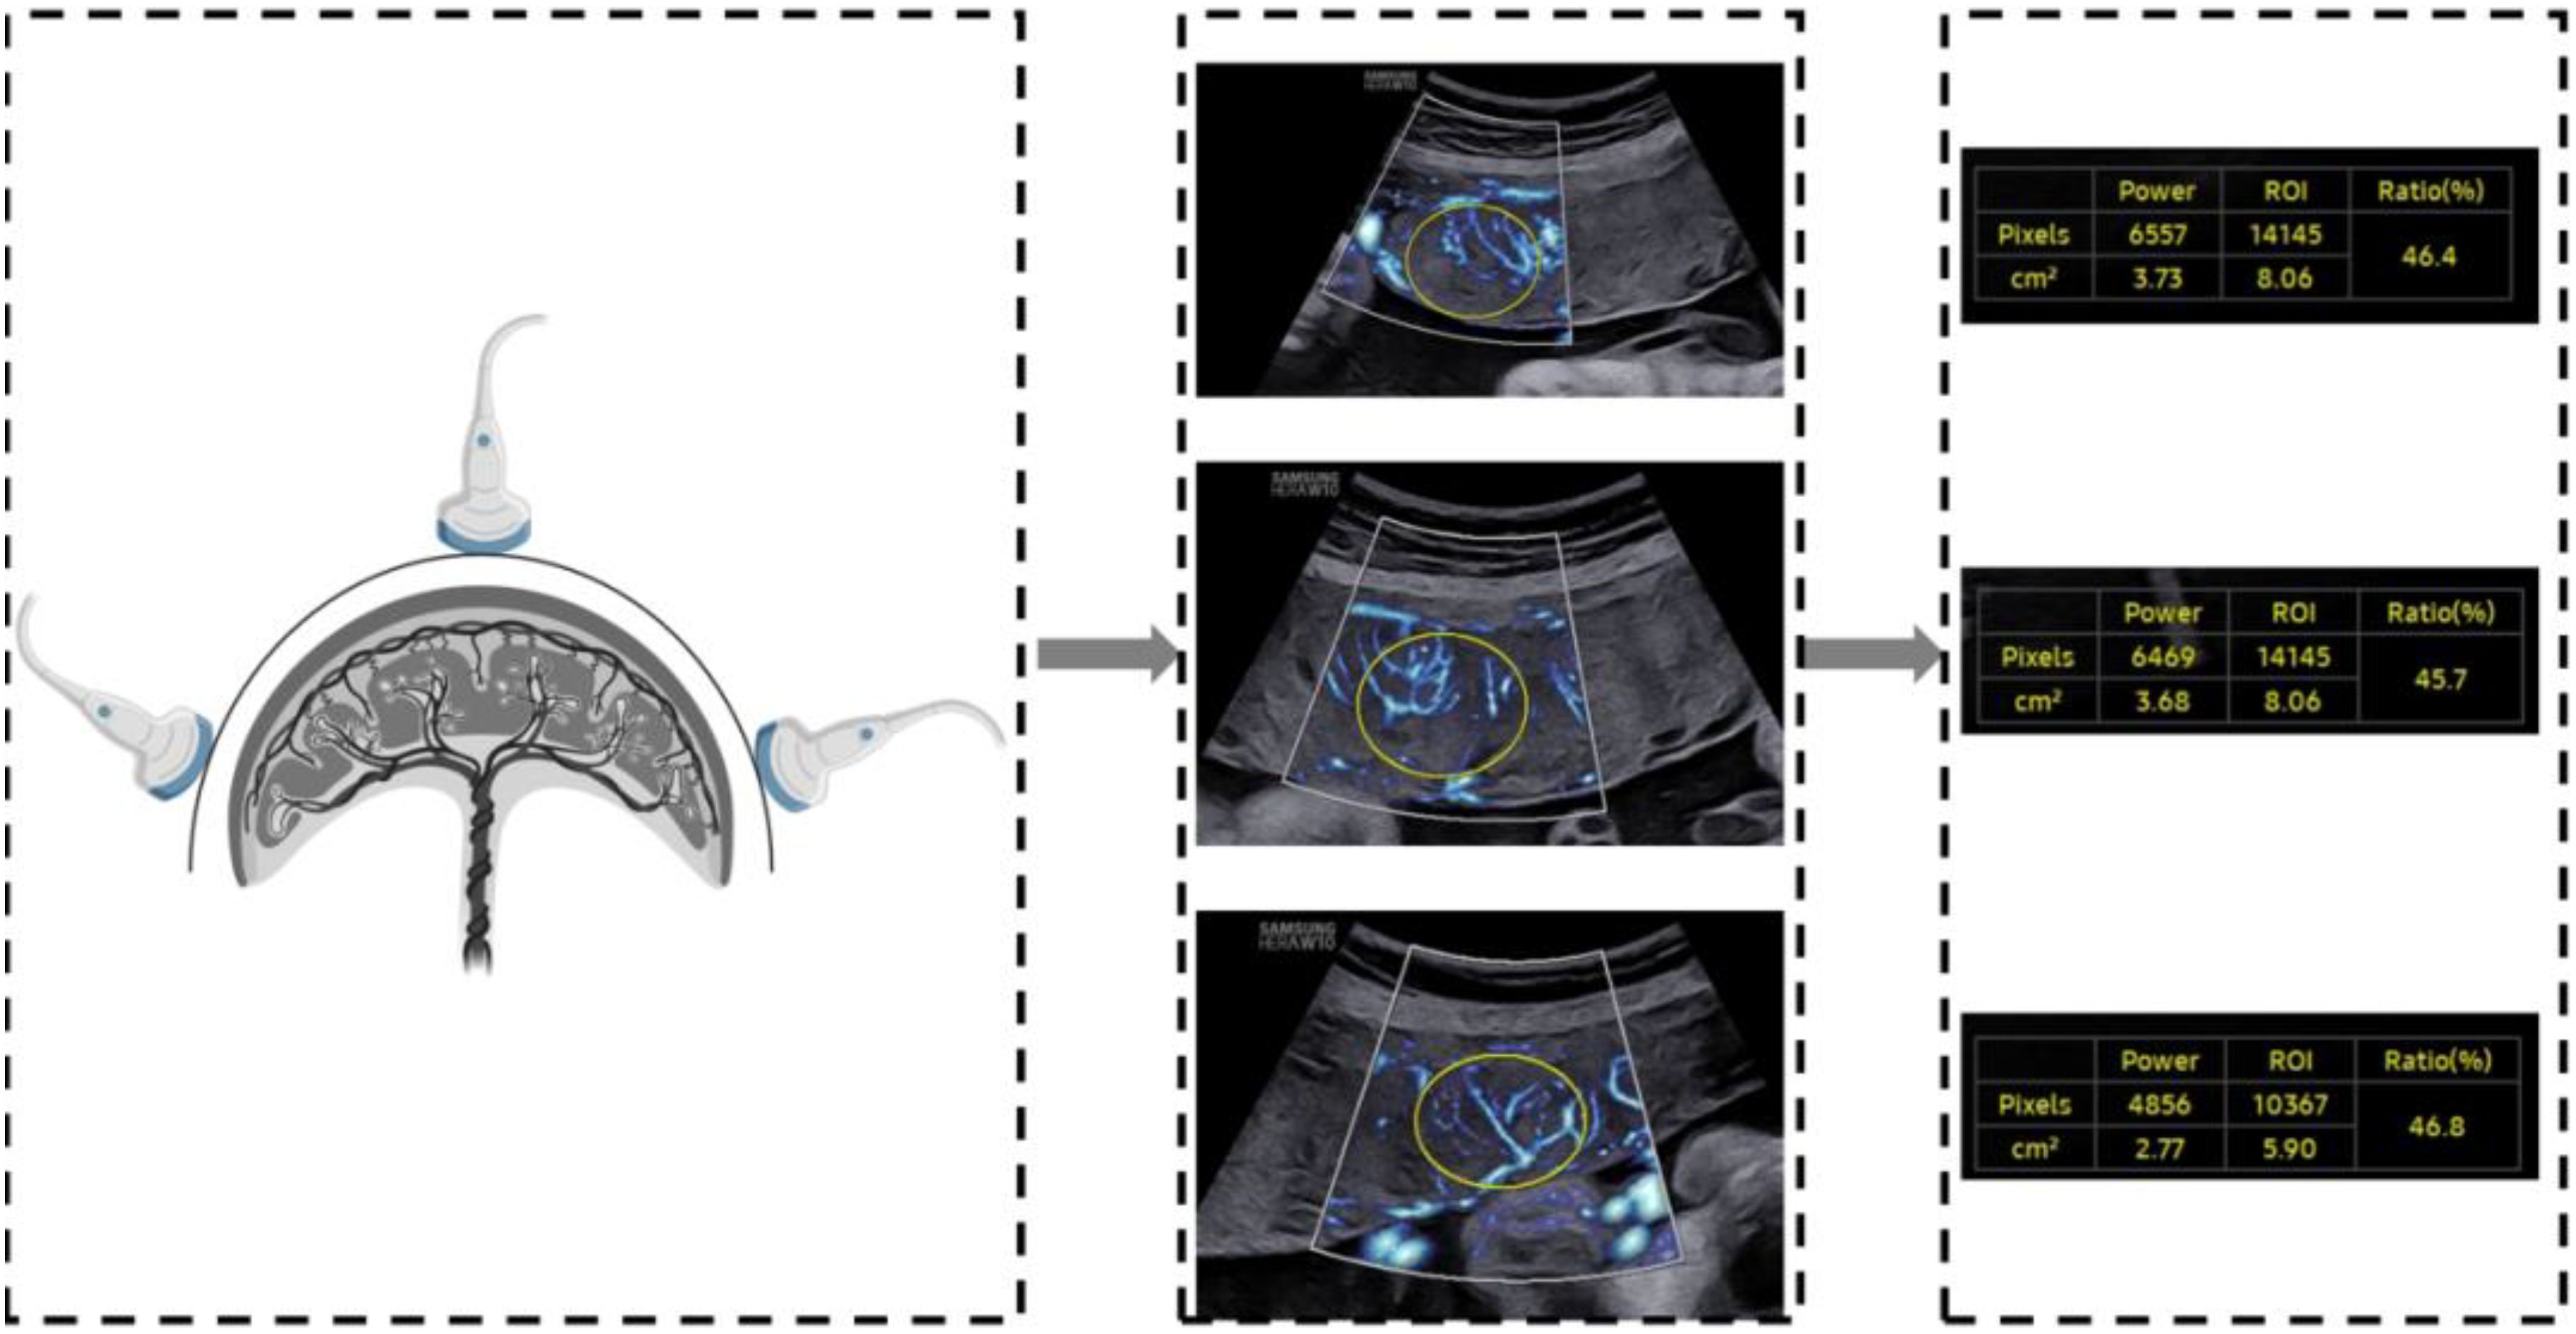

A two-dimensional transabdominal scan was performed to acquire a distinct image of the sagittal plane of the placenta. The instrument was set to the MV-Flow mode (frame avg = 8, dynamic range = 27, smooth = 1, filter = 3, sensitivity = 32, color map = 2), with the mechanical index and the thermal index adjusted to safe levels. The area of interest (ROI) was traced elliptically and displayed in square centimeters. Two-dimensional ultrasound images of the placental microvascular perfusion of the upper, middle, and lower sites were obtained, and the MVI values of the placenta were measured automatically (Figure 1). To represent the overall vessel microperfusion of the placenta, the mean MVI value (MVImean) of the three sites was calculated for analysis. All placental MV-Flow analyses were performed by the study sonographer who underwent training with radiologist expertise in placental microvascular flow imaging and was blinded to maternal characteristics and GDM status. To assess the reproducibility of measurements, 40 cases from the control and GDM group were selected by stratified samplings, and measurements were taken by an expert investigator and then by the study sonographer, both of whom were blinded to previous measurements.

Figure 1

Illustration depicting the MV-Flow imaging process utilizing ultrasound transducer positioned around the placenta. Three corresponding ultrasound images are presented, each annotated with the region of interest (ROI) and MVI.

Figure 1. Demonstration of placental assessment using MV-Flow.